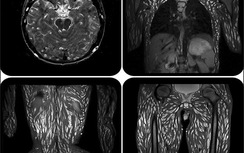

Cha mẹ cần lưu tâm thăm khám cho trẻ khi thấy trẻ lác mắt, sụp mi... phòng nhược thị cho trẻ